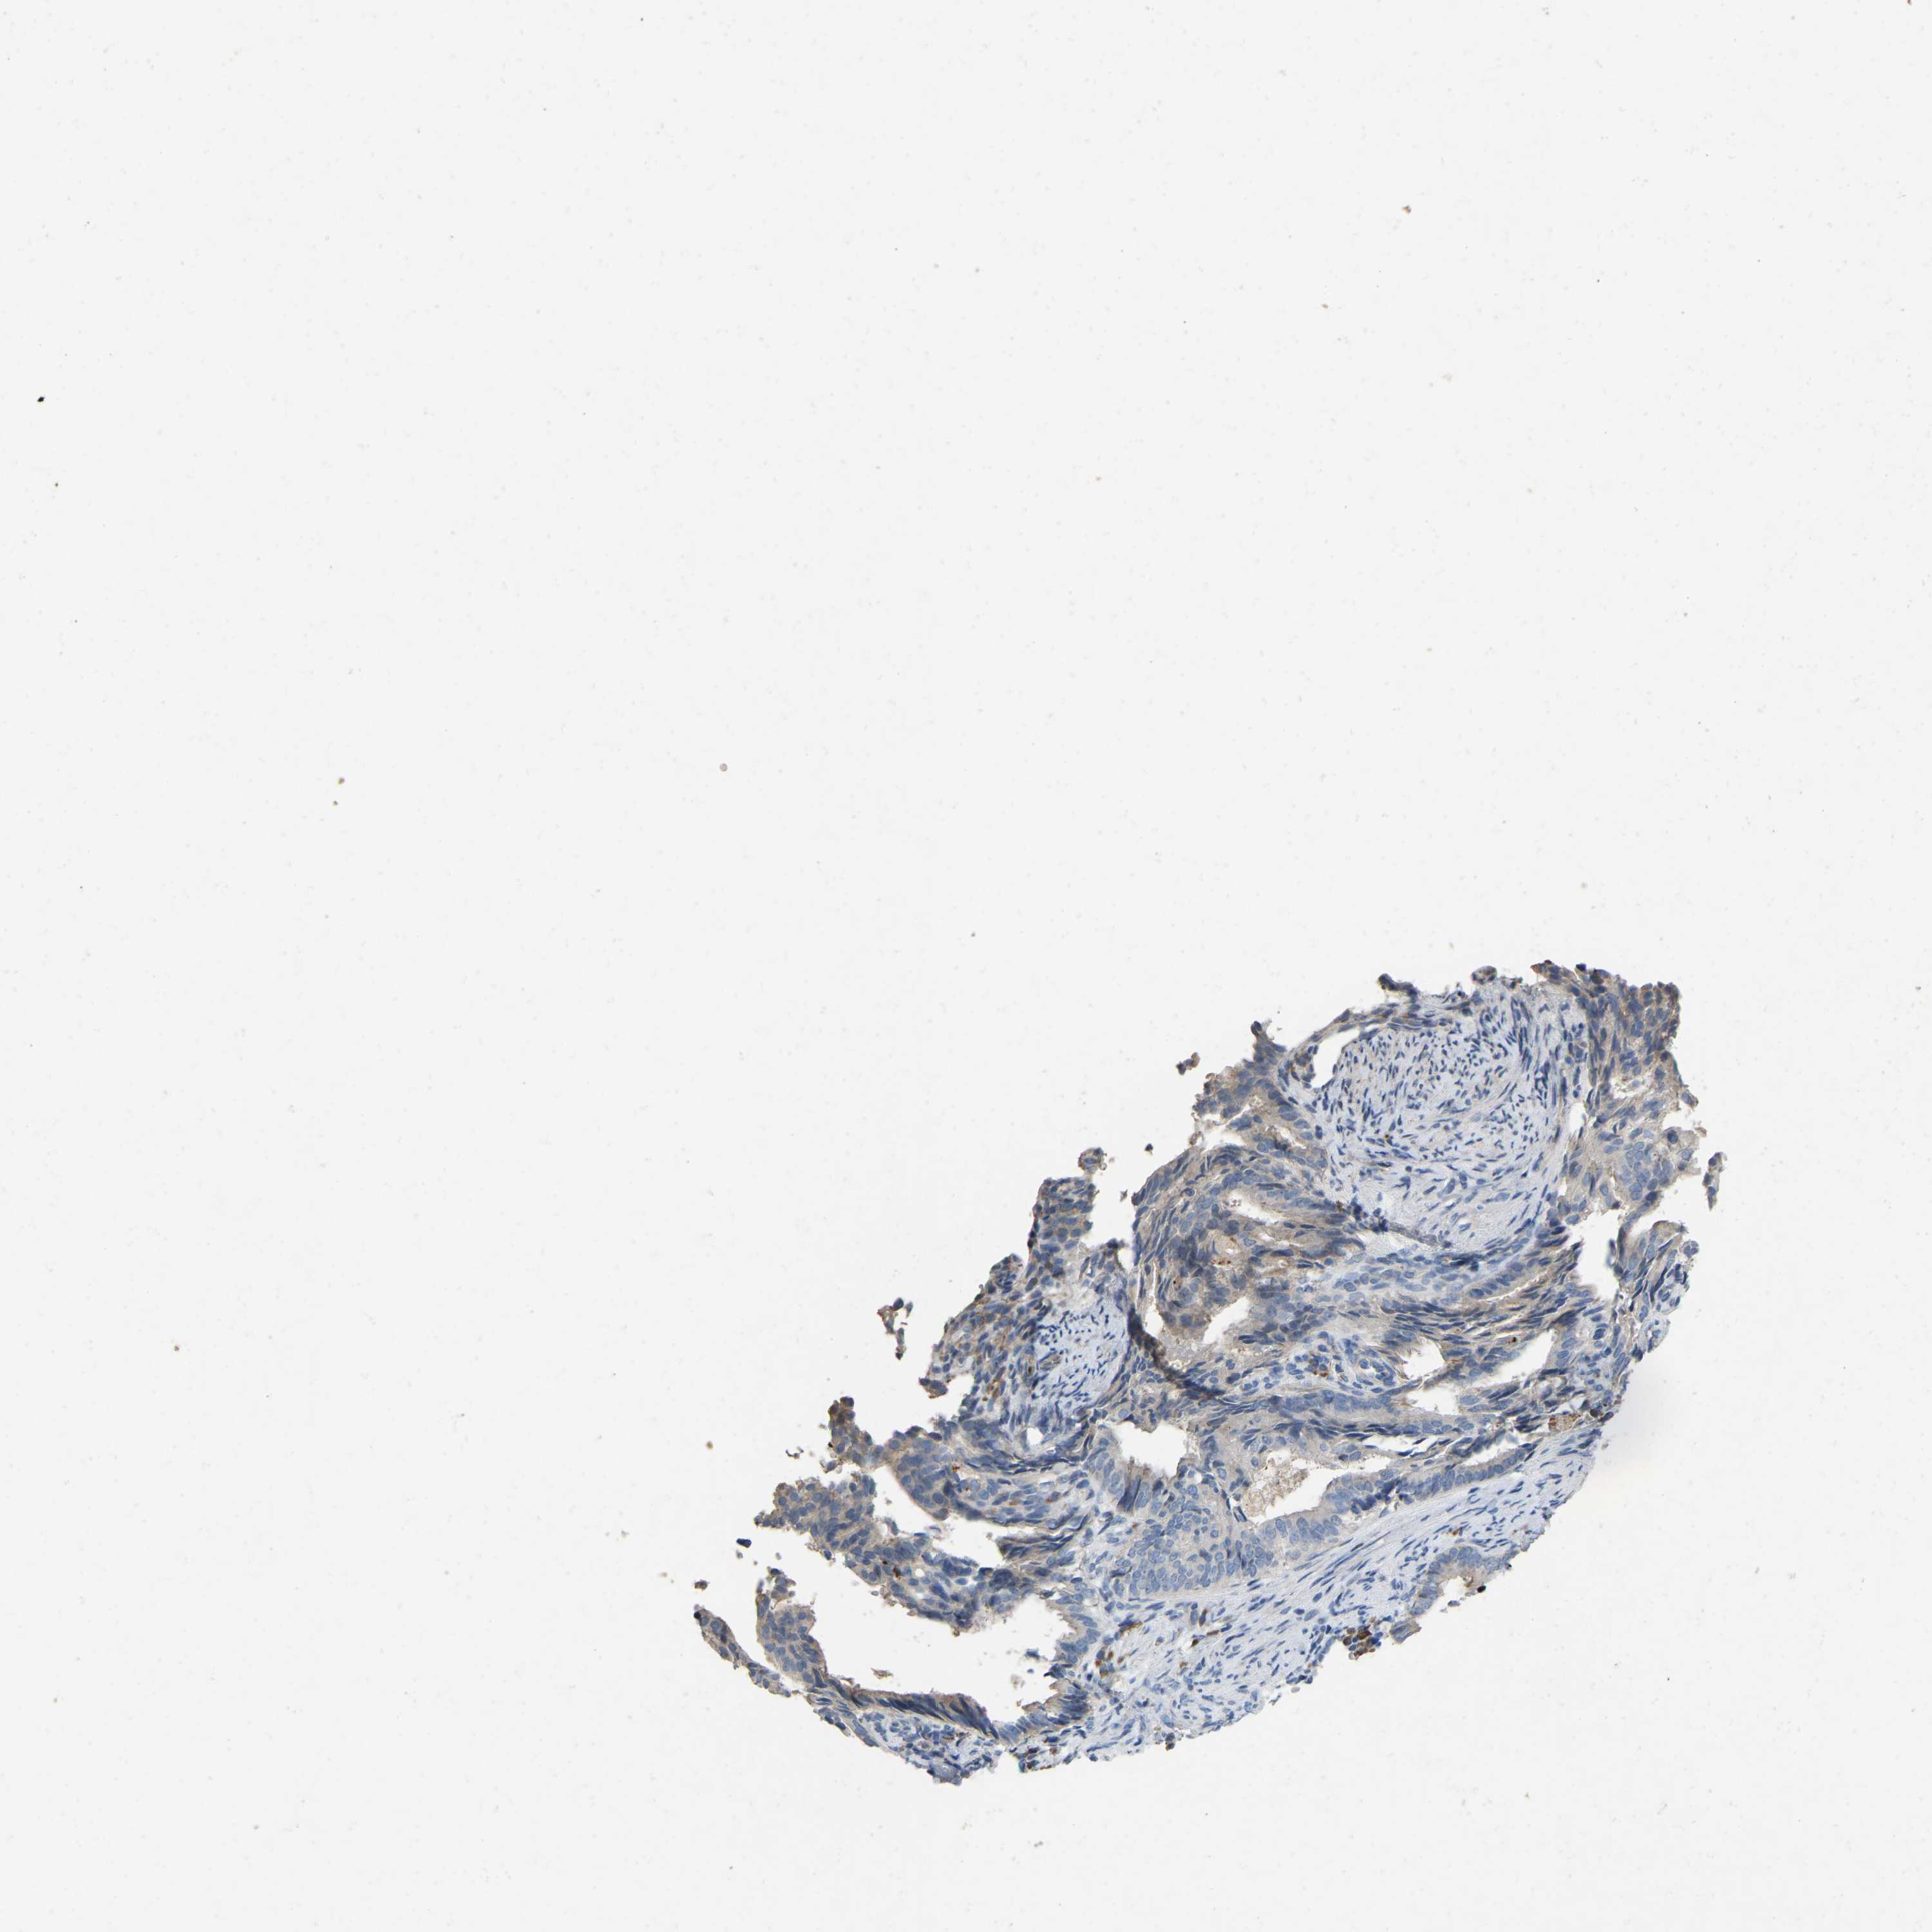

ENDOMETRIAL CANCER - Protein expressioni

A mouse-over function shows sample information and annotation data. Click on an image to view it in a full screen mode. Samples can be filtered based on level of antibody staining by selecting one or several of the following categories: high, medium, low and not detected. The assay and annotation is described here.

Note that samples used for immunohistochemistry by the Human Protein Atlas do not correspond to samples in the TCGA dataset.

Antibody stainingi

Antibody staining in the annotated cell types in the current human tissue is reported as not detected, low, medium, or high, based on conventional immunohistochemistry profiling in selected tissues. This score is based on the combination of the staining intensity and fraction of stained cells.

Each image is clickable and will lead to virtual microscopy that enables deeper exploration of all samples and also displays staining intensity scores, fraction scores and subcellular localization as well as patient and tissue information for each sample.

Antibody CAB019436

Staining

High

Medium

Low

Not detected

Intensity

Strong

Moderate

Weak

Negative

Quantity

>75%

75%-25%

<25%

None

Location

Nuclear

Cytoplasmic/membranous

Cytoplasmic/membranous,nuclear

Adenocarcinoma, NOS